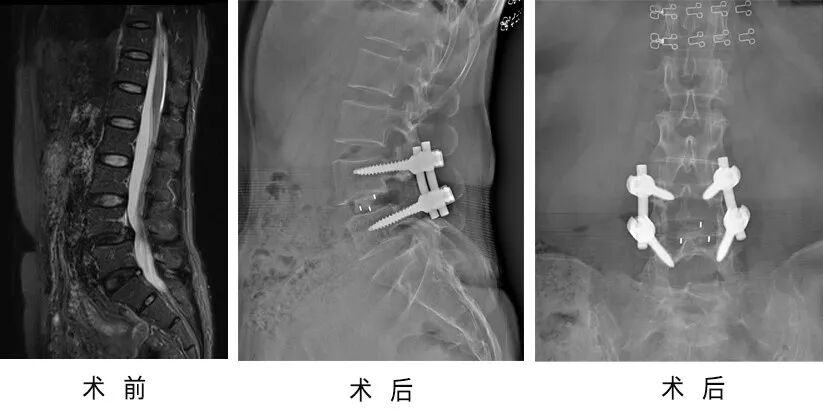

29歲的小周在2018年的年底發(fā)現(xiàn)右側(cè)髂腰部局部有一種腫塊并逐步增大,并伴有頭暈等不適,于今年1月在當(dāng)?shù)蒯t(yī)院就診進行了右側(cè)髂腰部腫物切開引流術(shù)。

今年4月,小周因為坐摩托車時顛簸導(dǎo)致腰骶部劇烈疼痛,腰部屈伸活動受限,行走不利,前來省級知名骨科專家、邦爾骨科集團首席專家、嘉興邦爾骨科醫(yī)院院長趙凱教授的專家門診就診,診斷為“腰椎結(jié)核伴椎旁膿腫”。

趙凱教授帶領(lǐng)脊柱外科團隊為小周順利的完成了“腰椎結(jié)核(L4、5)經(jīng)前外側(cè)入路病灶清除+取髂骨植骨融合釘棒內(nèi)固定術(shù)”,術(shù)后小周結(jié)核病灶徹底清除,恢復(fù)正常行走。

術(shù)前術(shù)后對比圖